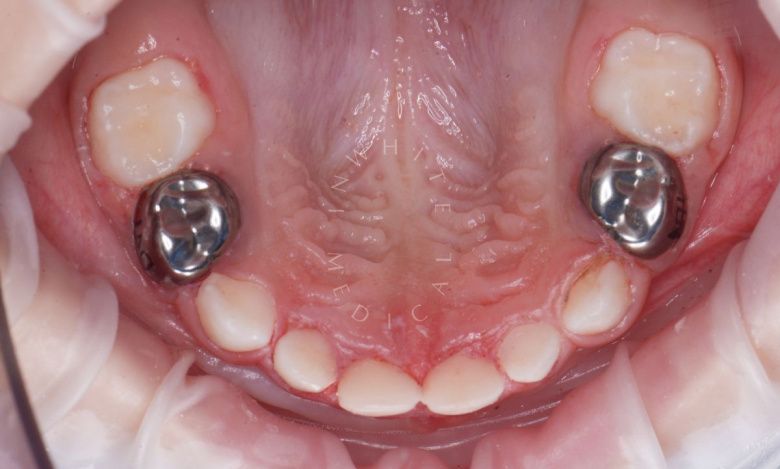

етская стоматология под наркозом Москва. Лечение молочных зубов и установка металлических коронок во сне - после процедуры